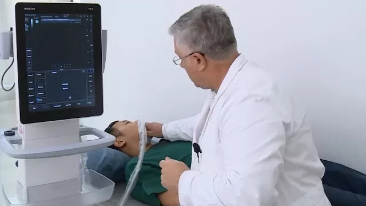

Sinds de oprichting van het bedrijf is Mindray voortdurend op zoek naar nieuwe manieren om het diagnostisch vertrouwen te vergroten. Resona 7 wordt aangestuurd door de meest revolutionaire ZONE Sonography?-technologie. Zijn nieuwe ZST+-tilt de kwaliteit van ultrasoundbeeldvorming naar een hoger niveau door middel van zoneacquisitie en kanaalgegevensverwerking.

Naast de hoogwaardige beeldvormingskwaliteit verbetert de Resona 7 tevens de klinische onderzoeksmogelijkheden met de revolutionaire V Flow voor vasculaire hemodynamische evaluatie, en de intelligentste vlakacquisitie van een 3D-gegevenssets voor de diagnose van het foetale, centrale zenuwstelsel. Met zijn combinatie van de meest intu?tieve, op vingerbewegingen gebaseerde multi-aanrakingsbediening en alle essenti?le klinische functies loopt de Resona 7 voorop in de nieuwe golven van ultrasoundinnovatie.